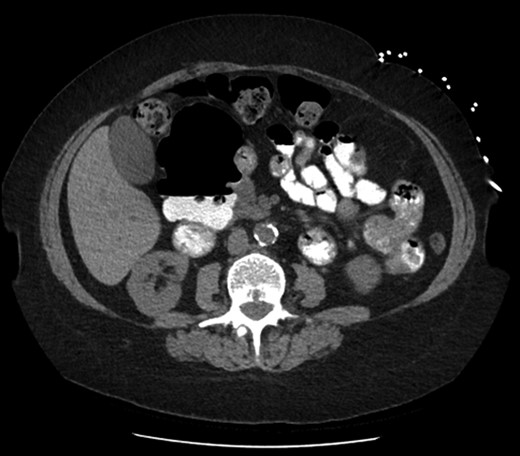

Axial slice of computed tomography (CT) scan—giant diverticulum with air-fluid level containing oral contrast.

On investigation they be mistaken for abscesses with an air-fluid level or thought to be a separate loop of bowel [3]. As noted with our patient, she had multiple modalities of abdominal imaging that had not previously reported this diverticulum. Hers was thought to be asymptomatic and therefore did not need emergent management, however it should be kept in mind as a potential cause of acute abdomen in the future.